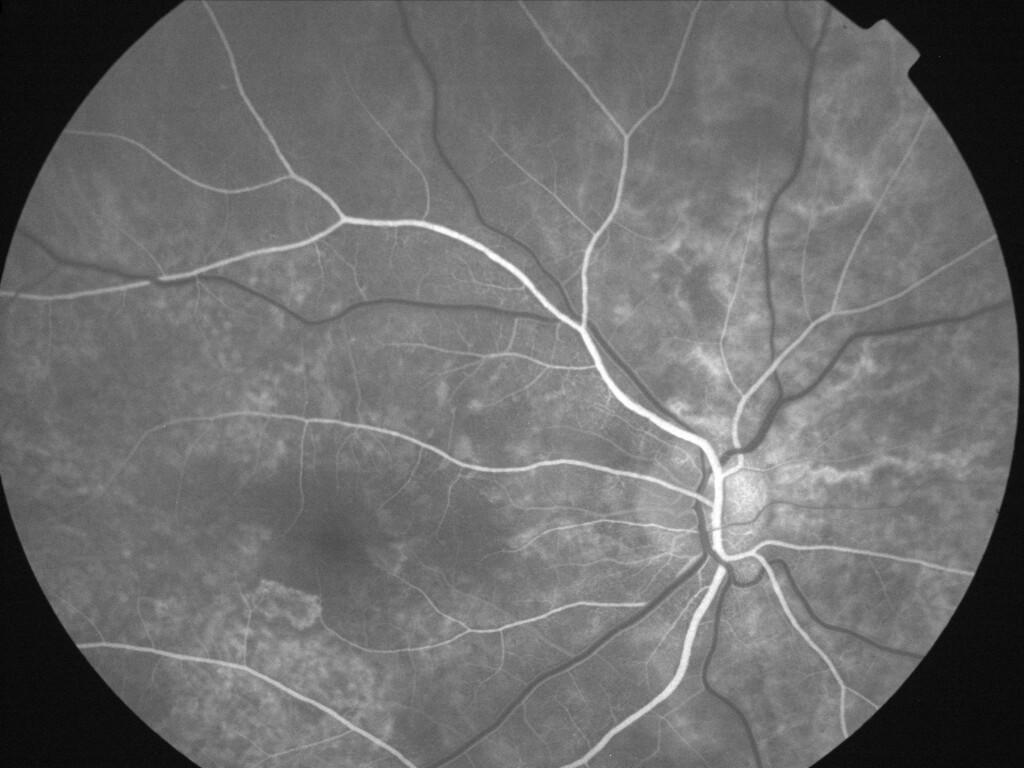

ASSOCIATION STRIES ANGIOIDES ET DYSROPHIE MACULAIRE RETICULEE

NEOVASCULARISATION